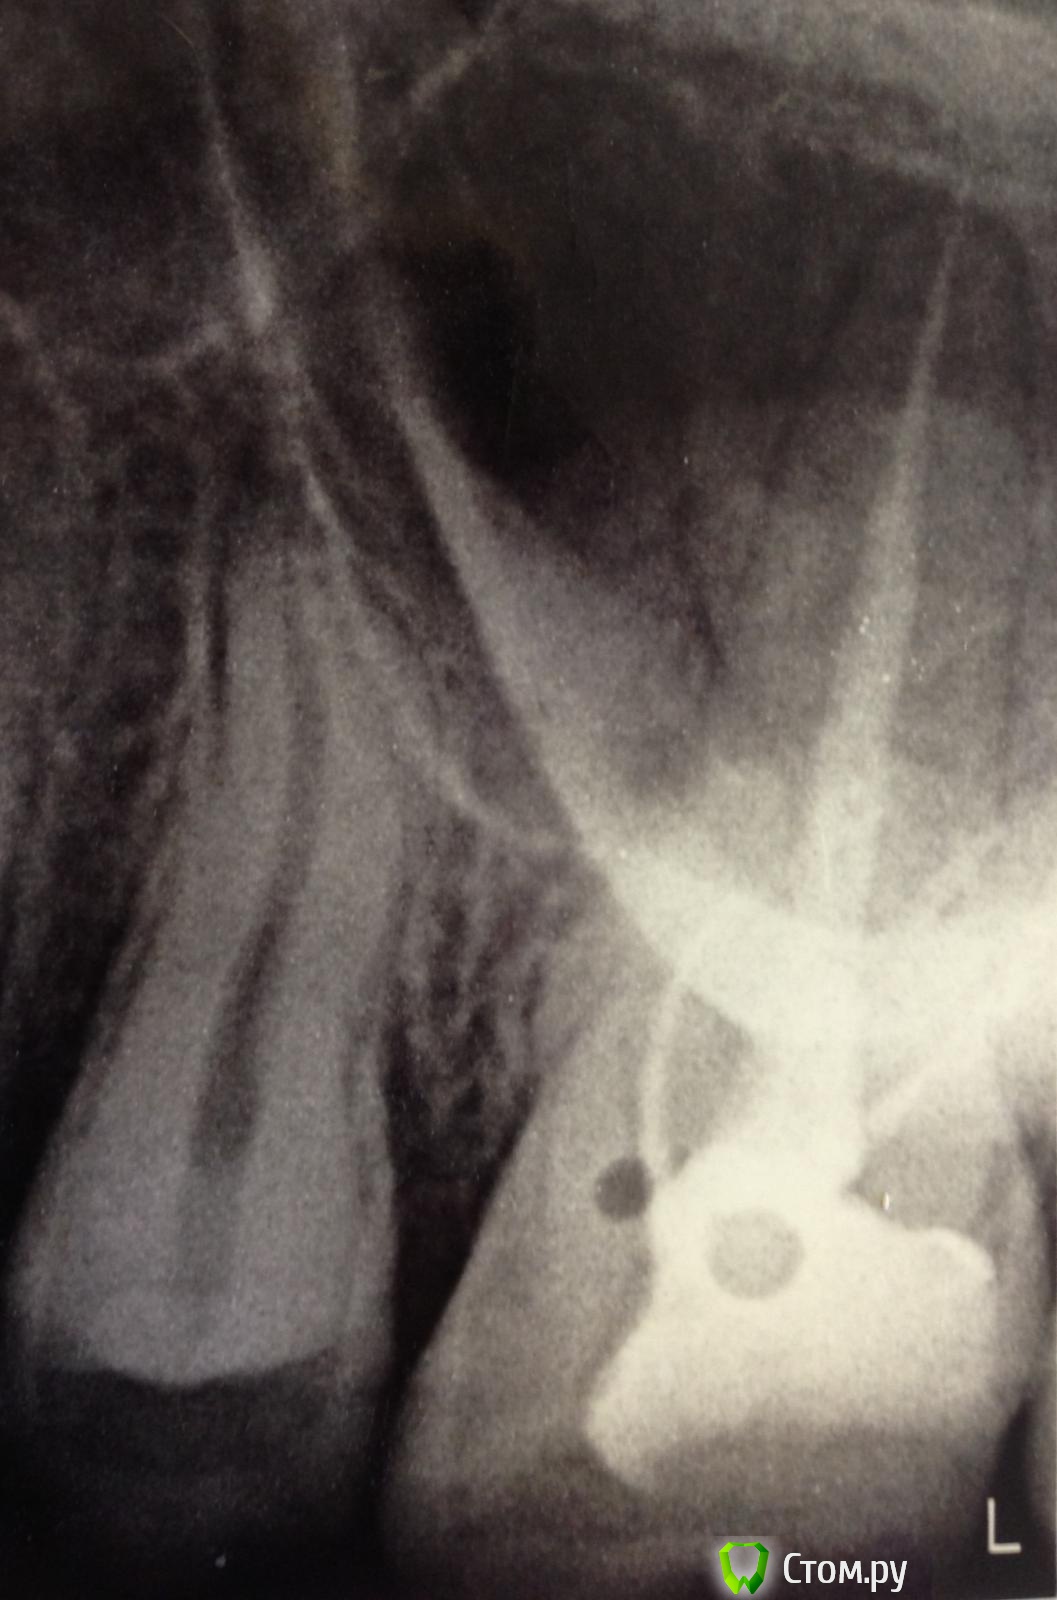

SSTi Опубликовано 20 октября, 2014 Автор Поделиться Опубликовано 20 октября, 2014 45. Пульпит. Латералька прикольная получилась. 3 Ссылка на комментарий